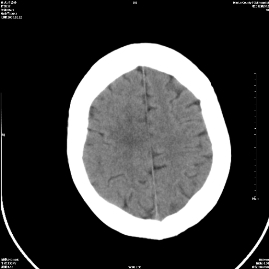

标题: CT18282:右顶叶半卵圆中心低密度影考虑脑梗塞 [打印本页]

标题: CT18282:右顶叶半卵圆中心低密度影考虑脑梗塞

有梗塞?

哪有梗塞,那是机器伪影吧!

不会是机器伪影吧,做个mr吧

机器伪影

每层都有是伪影

伪影?肝豆状核变形?一氧化碳中毒?梗塞?

未见异常

右顶叶半卵圆中心低密度影考虑脑梗塞,建议mri。

伪影

多为伪影——扫个水模看看。

伪影.

支持梗塞表现

伪影!

脑梗塞

右顶叶半卵圆中心低密度影考虑皮层下动脉硬化性脑病,建议结合临床。

右侧颞顶叶都有病灶,考虑为腔梗,建议mri检查进一步证实。

伪影?不放心做个mr吧。

考虑脑梗塞。